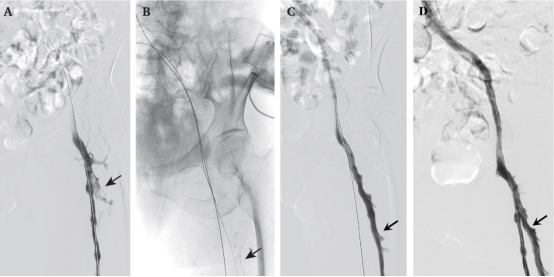

image.png 黑色箭头所指处即为股深静脉,通过介入治疗后血栓彻底清除